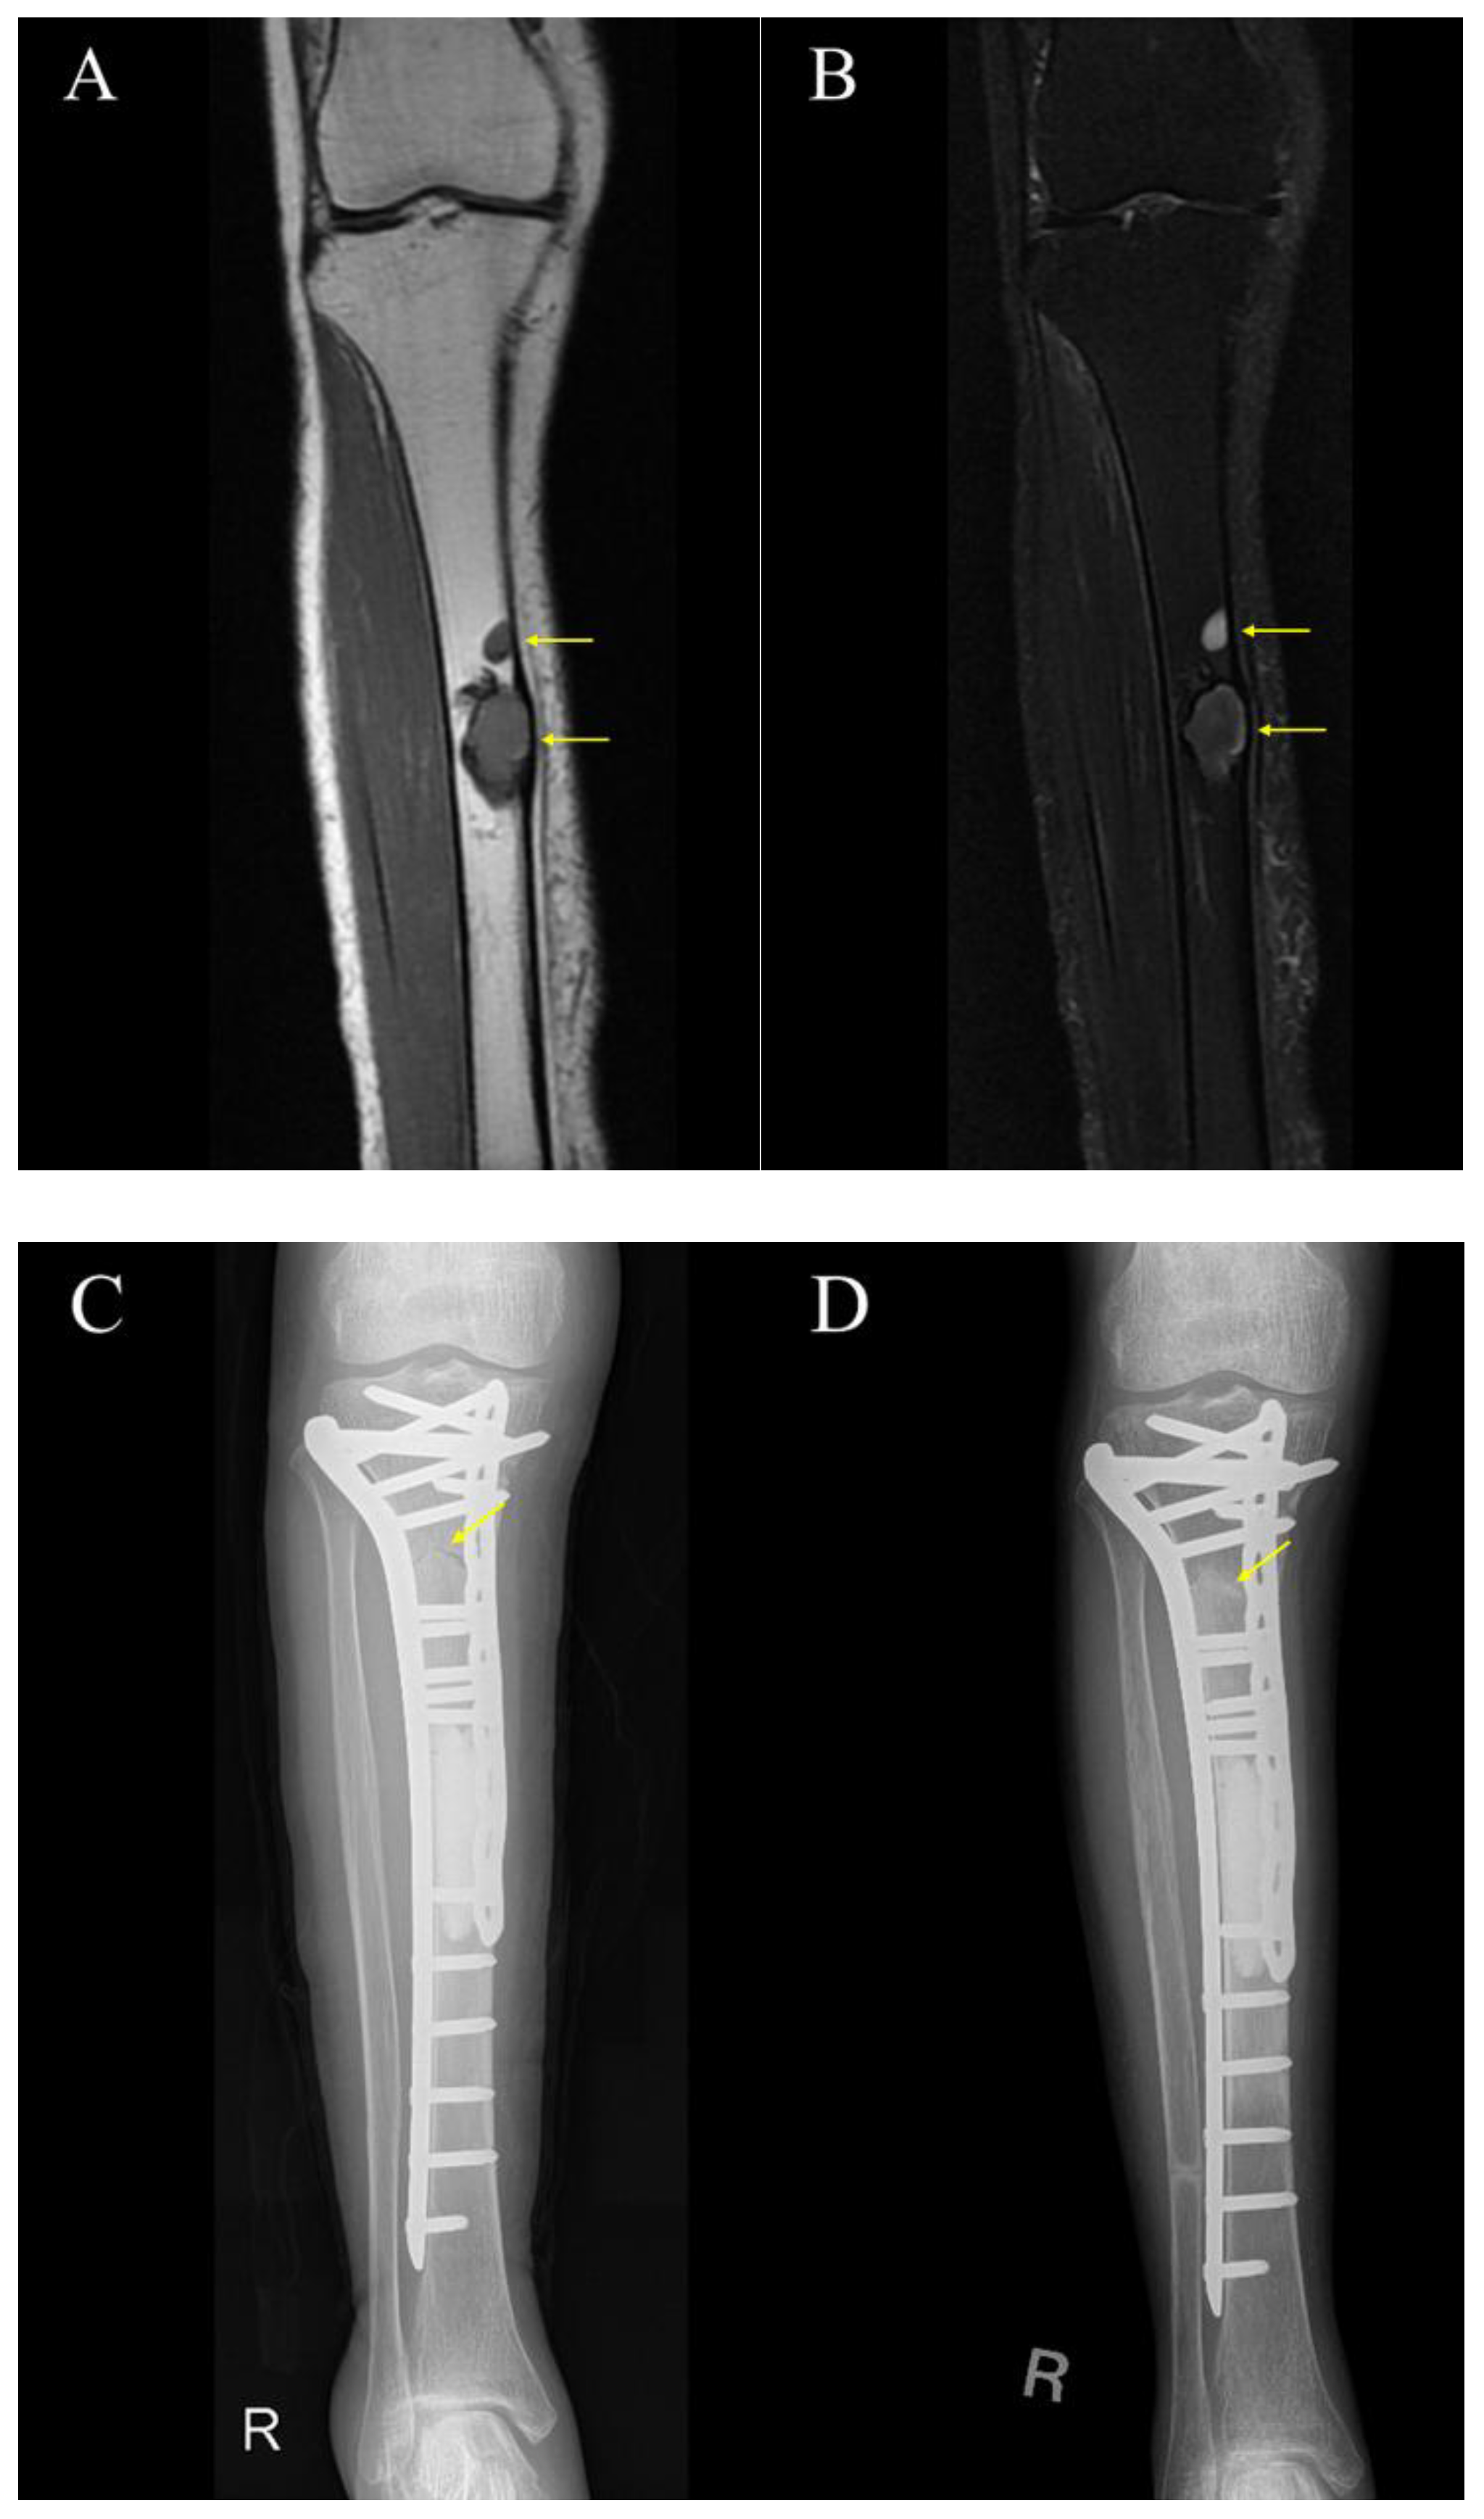

3.3. Cases